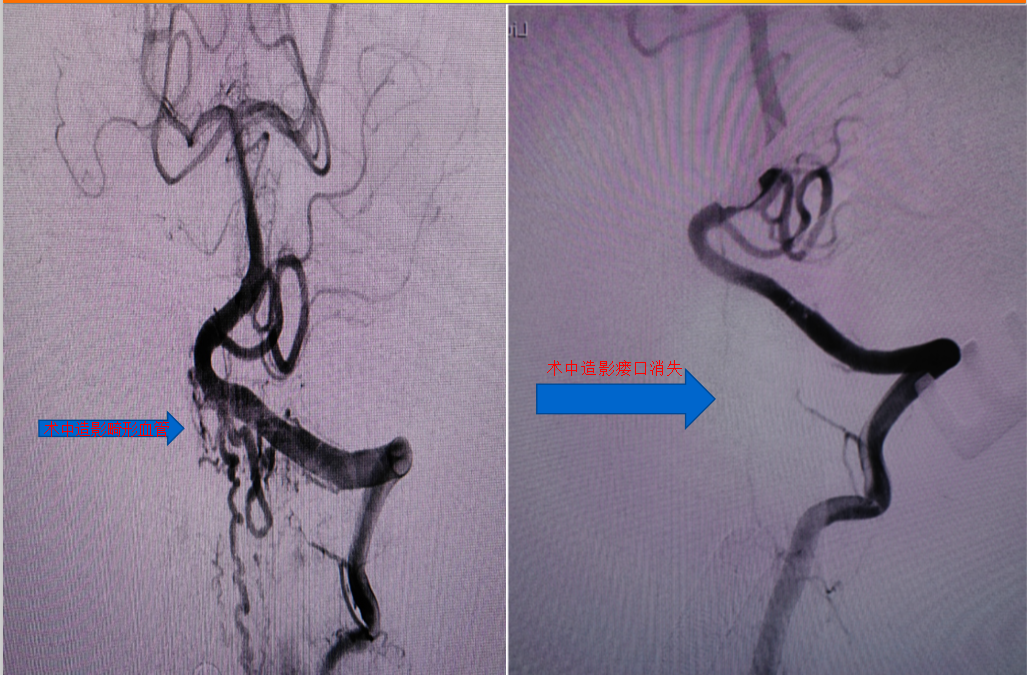

经过神经外科李学东主任手术团队的努力,手术顺利实施,团队成员有条不紊进行左侧桡动脉置管至左椎动脉、俯卧位碳纤维头架固定、特殊体位消毒、左侧枕部旁正中入路等一系列操作,通过术中标记造影,滑轨CT定位,在脑干及周围神经血管的周围,循异常迂曲扩张的引流静脉找到瘘口,予以夹闭烧灼,术中DSA证实畸形血管已消失、滑轨CT证实无颅内出血等异常。

术中脑血管造影显示动静脉瘘及异常引流静脉消失

术中滑轨CT未见出血以及脑梗